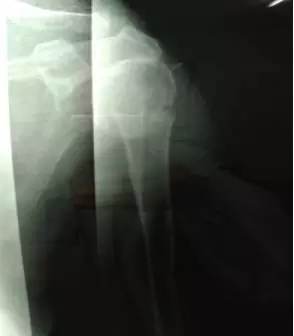

鮑阿婆年紀大了,體質又差,難以承受手法復位的巨大痛苦,因此在幫鮑阿婆完善相關檢查后,正骨科醫(yī)生專門進行了病歷討論,制定了周密的手法整復方案。在入院后第二天,就在臂叢麻醉下給予手法整復。雖然阿婆的骨折嚴重,手法復位困難太大,但正骨科醫(yī)生憑借自己精湛的醫(yī)術及豐富的臨床經(jīng)驗,順利的幫助鮑阿婆把骨折位置復好了。

整復后復查X線片,骨折端位置良好。

鮑阿婆及家人看過片子后也十分滿意,“都說廣安醫(yī)院醫(yī)生的技術真是好,早知道3年前右手骨折在你們這里看,就不用吃那么多苦了”。鮑阿婆表示。

整復后